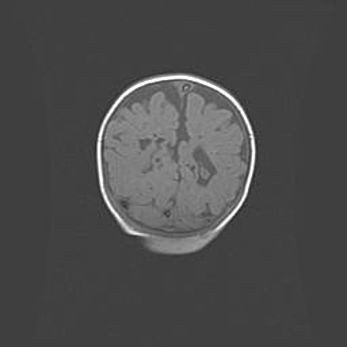

Наружная гидроцефалия с возможной атрофией височных областей.

Возраст: 28 дней

Вес: 3670 г

Пол: мужской

Окружность головы: 38 см

Срок гестации: 40 недель

Гидроцефалия головного мозга у новорожденных – это заболевание, которое характеризуется скоплением избыточного количества спинномозговой жидкости в желудочковой системе головного мозга в результате затруднения её перемещения от места выработки к месту поглощения в кровеносную систему или вследствие нарушения абсорбции. При открытой наружной форме гидроцефалии у новорожденных расширяются и переполняются субарахноидные пространства.

При нормотензивных  формах,  которые,  как  правило,  являются  следствием  перенесенных ишемических  повреждений  паренхимы  мозга,  возможно  сочетание микроцефалии  с нормотензивной гидроцефалией. В основе данных изменений лежит атрофия больших полушарий с преимущественной  локализацией  в  лобно-височных  областях.